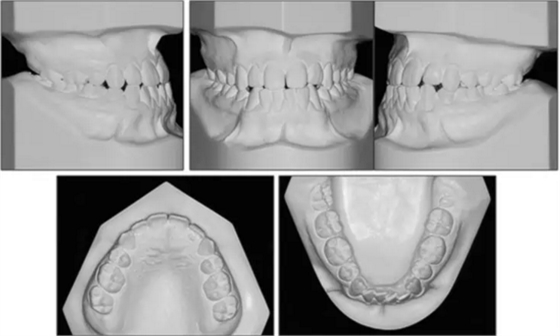

口內(nèi)相示:尖牙、磨牙完全I(xiàn)II類關(guān)系,覆蓋2mm,覆合端端關(guān)系,上頜中線左偏2mm,下頜牙列擁擠5mm。

口內(nèi)相及模型:雙側(cè)磨牙、尖牙I類關(guān)系,良好的牙尖交錯關(guān)系,覆合、覆蓋正常。